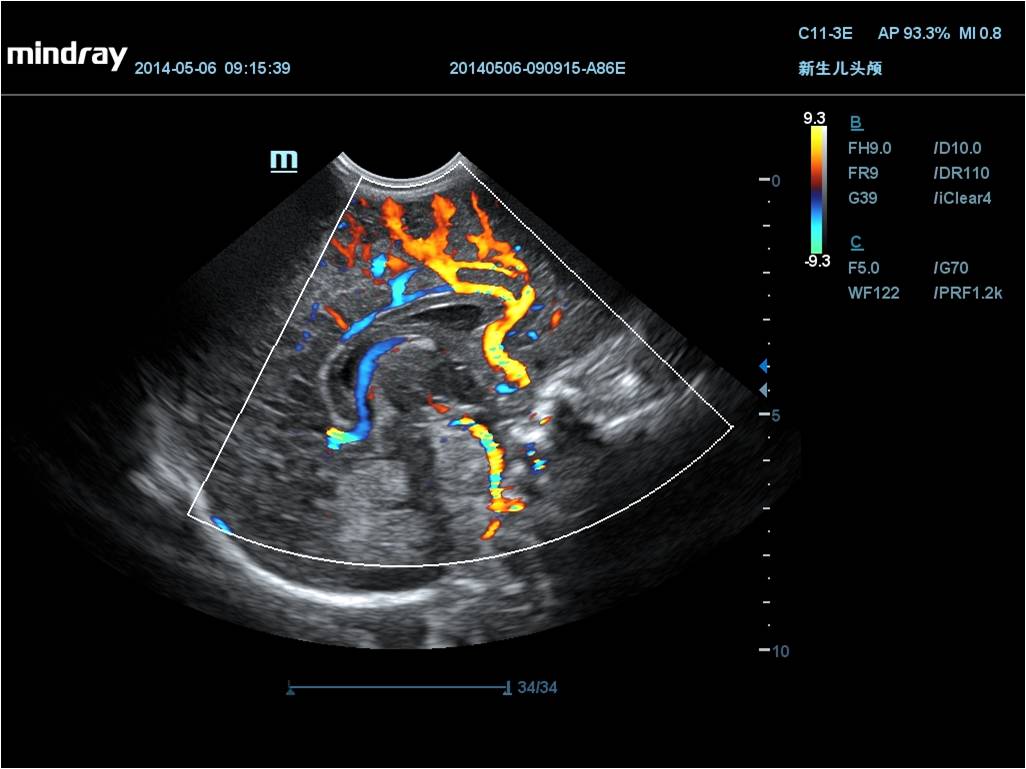

Mindray DC-70 Exp с технологией X-Insight – это узи-аппарат для высококачественной диагностики. Преимущества: высокая эффективность, точность визуализации, результат в «одно касание» с экспертными датчиками. Рекомендуется для государственных учреждений.